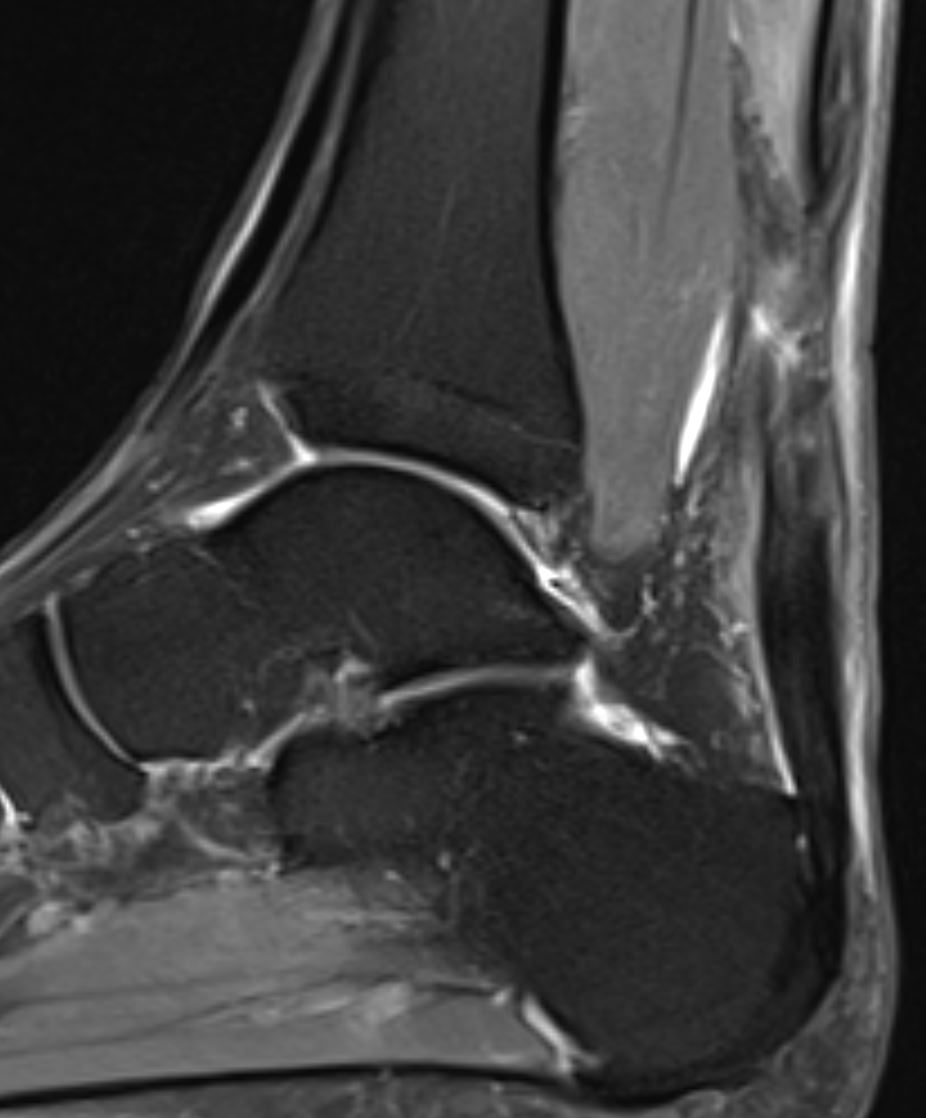

Home Schwerpunkte Krankheitsbilder Achillessehnenruptur MRT Bild 4 Wochen alte Achillessehenruptur nach der Operation bei Achillessehnenriss MRT Bild 4 Wochen alte Achillessehenruptur nach der Operation bei Achillessehnenriss MRT Bild 4 Wochen alte Achillessehenruptur nach der Operation bei Achillessehnenriss